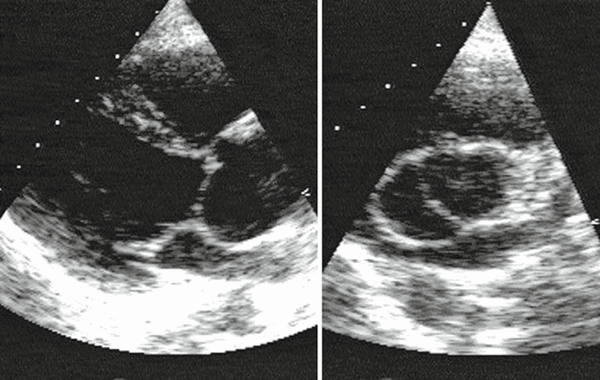

Эхокардиография - важный метод в диагностике аортальной недостаточности. Наиболее часто обнаруживаются следующие изменения:

- дилатация и гипертрофия левого желудочка;

- увеличение амплитуды движения межжелудочковой перегородки и задней стенки левого желудочка;

- увеличение переднезаднего размера левого предсердия (в систолу - до 55 мм, в диастолу - до 70 мм);

- отсутствие диастолического смыкания створок аортального клапана.